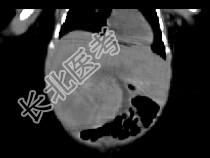

- 单项选择题男,刚刚出生5天, 上腹部膨隆,CT所见如图, 最可能的诊断为 ( )